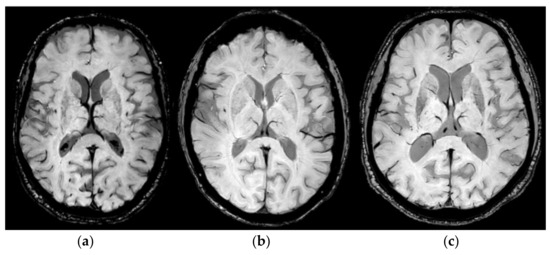

In Figure 1, we report a comparison of the target identification obtained by using stereotactic coordinates (a), STV identification (b), and the lesion of the target after sonication (c).

Figure 1.

Target identification by using stereotactic coordinates (a), STV visualization (the arrow indicates the vein) by using the SWI sequence (b), the real position of target obtained after sonication and evaluated after 4 weeks by using the SWI sequence (c).